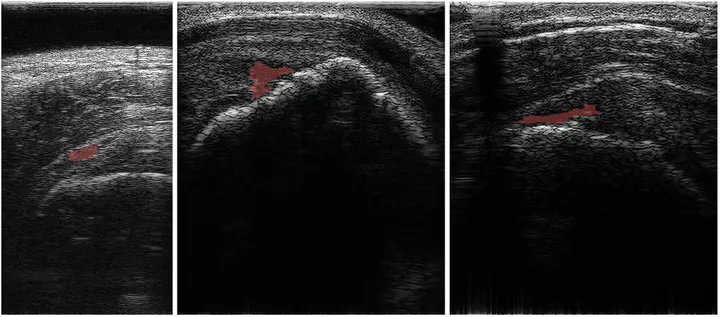

Medical ultrasound imaging is a key diagnostic tool across various fields, with computer-aided diagnosis systems benefiting from advances in deep learning. However, its lower resolution and artifacts pose challenges, particularly for non-specialists. The simultaneous acquisition of degraded and high-quality images is infeasible, limiting supervised learning approaches. Additionally, self-supervised and zero-shot methods require extensive processing time, conflicting with the real-time demands of ultrasound imaging. Therefore, to address the aforementioned issues, we propose real-time ultrasound image enhancement via a self-supervised learning technique and a test-time adaptation for sophisticated rotational cuff tear diagnosis. The proposed approach learns from other domain image datasets and performs self-supervised learning on an ultrasound image during inference for enhancement. Our approach not only demonstrated superior ultrasound image enhancement performance compared to other state-of-the-art methods but also achieved an 18% improvement in the RCT segmentation performance.